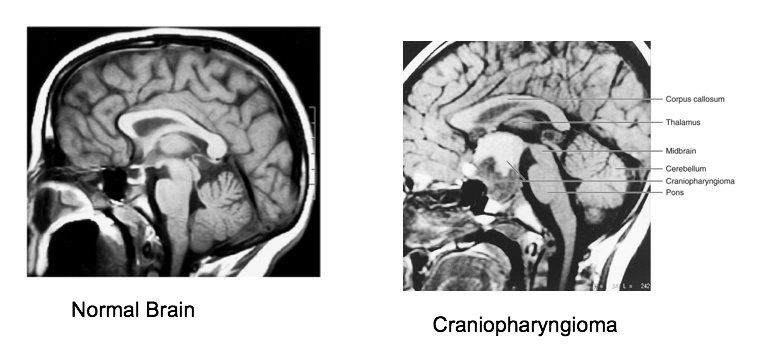

Craniopharyngioma

_ Benign tumor of pituitary gland, Derived from remnants of Rathke’s pouch. Instead of apoptosis, the remnant proliferate, , form cyst, and calcified. White and shiny. If occupy too much space (headache), must be removed.,

_Surface ectoderm in cyst because derived from Rathke's pouch..

_Symptoms are from compression of brain tissues:

Hypopituitarism

Headache, visual field defects

Behavioral change from frontal lobe dysfunction..

_Bimodal distribution of occurrence:

5-14

65-74.,